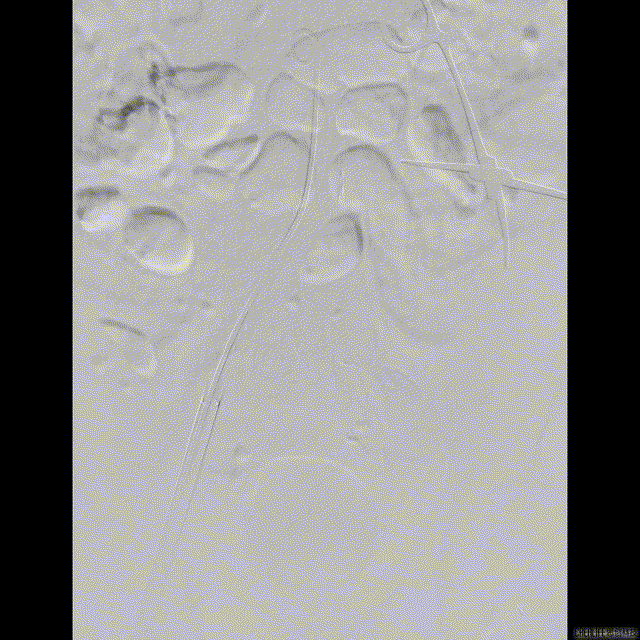

解剖上,这个患者虽然是右无融合的二叶瓣,但是右窦发育较小,形态上接近0型二叶瓣,瓣上钙化中,且集中在左窦,接近左右瓣叶联合部。瓣环及流出道平面较大,而瓣上结构较小,瓣叶联合部距离只有26,这种情况下只能考虑根据瓣上结构进行选择瓣膜。目标瓣膜为26号,为了避免破坏瓣上结构,我们选择26瓣膜的下限20号瓣膜进行与扩张。因为主动脉弓和升主动脉角度问题,没有选择plus。20球囊扩张可以看到左窦钙化很硬,右无联合可以推开,没有反流,故选择26号瓣膜,高位释放。释放后瓣膜下滑到标准位,有明显的腰,故用20球囊进行后扩展。最后造影虽然有中度瓣周漏,但是考虑患者狭窄解除,且升主动脉人工血管限制了瓣膜的流出端,未再行瓣中瓣。术中撤除ECMO,辅助循环约1小时。

患者既往行全升主人工血管置换,为type1型二叶瓣畸形患者,瓣环28.7,左室流出道30.2,二叶瓣鱼嘴短径为26.6,重度钙化,左右冠分别为12.7与15.1,STJ30.8,升主均径人工血管为27.7,患者EF值极低,心功能极差,遂行ECMO辅助下TAVR术式。

根部解剖: